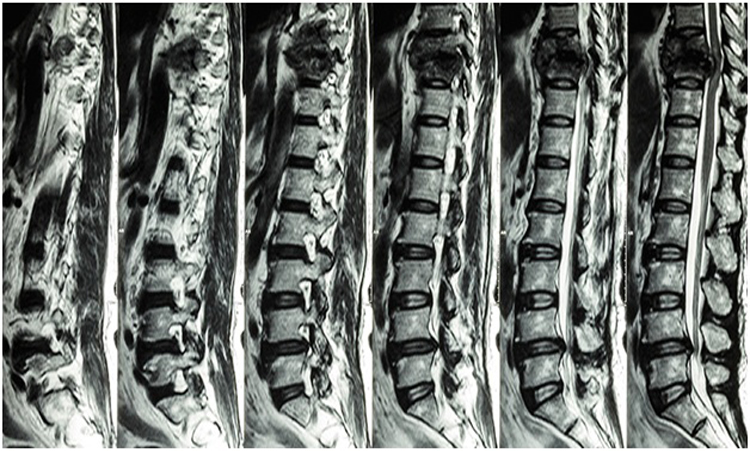

خواندن تصاویر ام آر آی نیاز به درک عمیق از آناتومی ستون فقرات و دیسکهای بینمهرهای دارد. تصاویر ام آر آی معمولاً به صورت مقاطع افقی، عمودی یا مایل از ناحیه کمر ارائه میشوند. در هر تصویر، پزشک باید به دنبال تغییرات غیرطبیعی در بافتها، مانند ورم، هرنی دیسک یا تغییرات دژنراتیو باشد. آشنایی با ساختارهای آناتومیکی، مانند مهرهها، دیسکها و عصبها، به پزشکان کمک میکند تا تغییرات را بهتر شناسایی کنند.

در تفسیر تصاویر ام آر آی، پزشکان باید به جزئیات دقیق توجه کنند. به عنوان مثال، در هرنی دیسک، ممکن است بخشهایی از دیسک به سمت خارج فشار بیاورند که میتواند به عصبها آسیب بزند. این نوع تغییرات در تصاویر به صورت برجستگی یا افتادگی دیسک مشاهده میشود. همچنین، علائم دیگری مانند تنگی کانال نخاعی، که ممکن است به دلیل بزرگ شدن لیگامانها یا دیسکها ایجاد شود، باید در نظر گرفته شوند. شناخت این علائم و نشانهها برای تشخیص صحیح ضروری است.